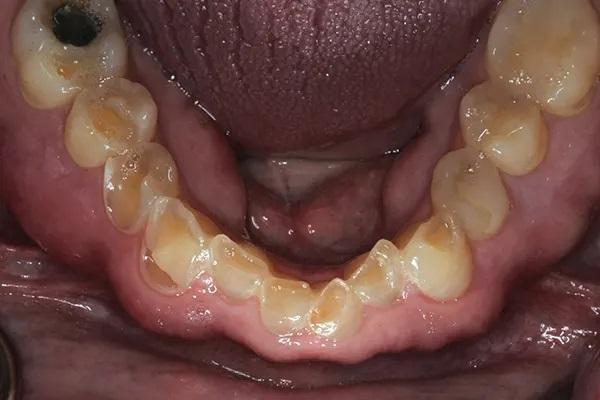

Фото 2: Максимальный бугорково-фиссурный контакт зубов-антагонистов до лечения. Обратите внимание на эрозию шейки и потерю эмали, не связанные с окклюзией.

Биомеханика: Сильная эрозия с обнажением дентина была отмечена на язычных поверхностях зубов с 1.4 по 2.4 (Фото 4), а также на лицевой и резцовой поверхностях зубов с 3.6 и 3.3 по 4.6 (Фото 5). В зубе 3.4 ранее проводилось лечение корневых каналов, а на зубах 3.6 и 3.5 были установлены большие реставрации, превышающие треть ширины их перешейка. На зубах с 1.3 по 2.3 имелись сколы. Хотя кариес в зубном ряду пациента не отмечался, потеря структуры зубов привела к серьезным структурным нарушениям во всех зубах, за исключением моляров верхней челюсти. На зубах 1.6 и 2.6 были выполнены окклюзионные реставрации из амальгамы, которые были приемлемы при незначительной эрозии на кончиках бугорков. Зубы 1.5 и 2.5 имели незначительную эрозию на окклюзионной поверхности.

Фото 5: Нижняя челюсть: вид с окллюзионной стороны до лечения Обратите внимание на сильную потерю эмали.